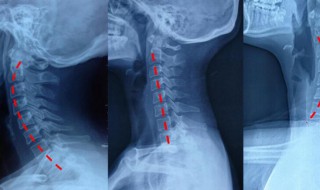

2、从侧方看人体在端坐或站立时的颈部似乎是直的,其实包绕于内的颈椎并不是直的,而是在其中段有一向前凸出的弧度。在医学上把这一向前的弧形凸起称为颈椎的生理曲度。通过X线片上的颈椎显像:沿此曲度走行,在各个颈椎椎体后缘都有形成的连续 、光滑的弧形曲线,医学上称之为颈椎曲度。当长时间不正确的坐姿、或是长时间的劳累、颈椎缺少活动、脊柱损伤、脊柱钙化等就会导致颈椎生理曲度变直。